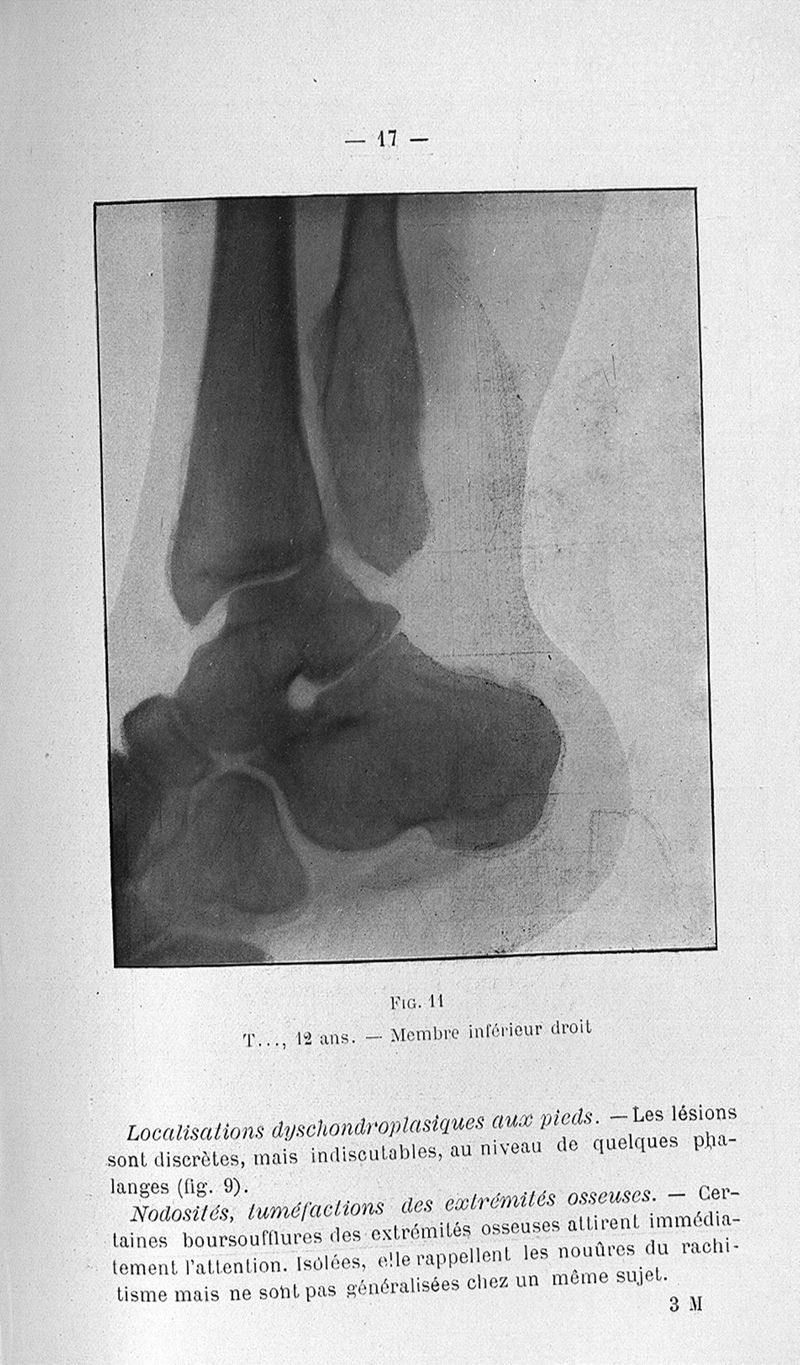

Molin, Henri Marie Louis.

Concours pour l'agrégation, 1904, section de chirurgie et accouchements. Titres et travaux scientifiques

Lyon, Impr. Paul Legendre & Cie, 1904.